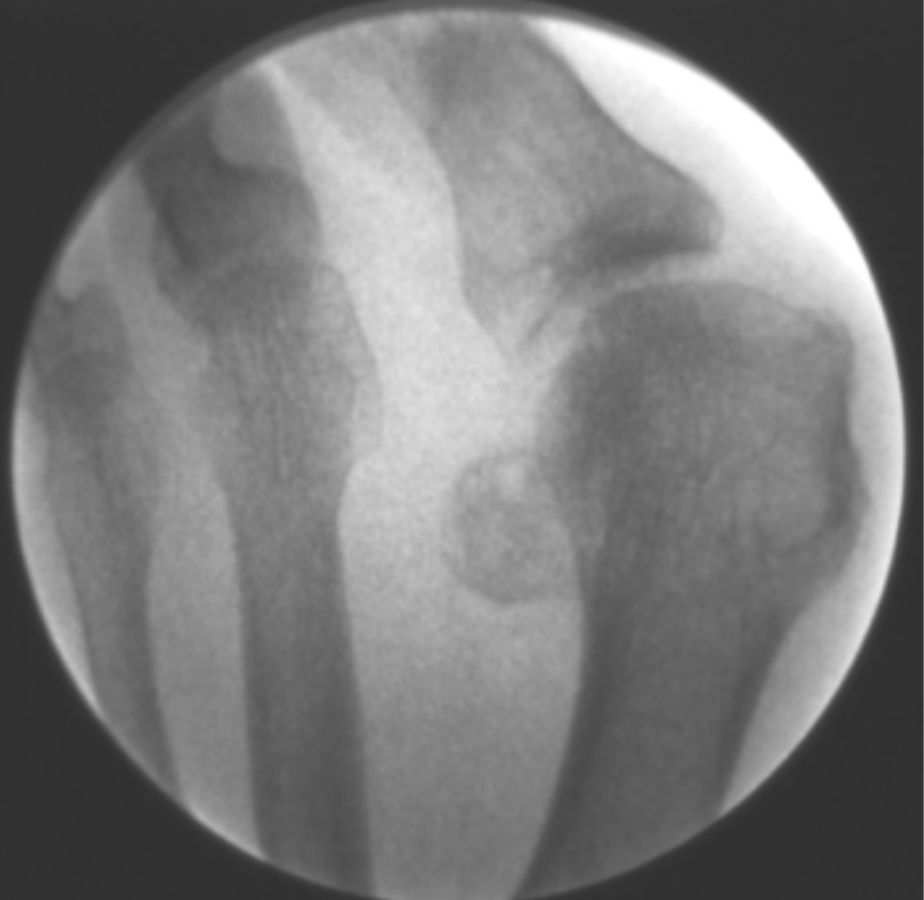

A continuación, mostramos algunas cirugías llevadas a cabo en nuestra clínica podológica.

ANTES

casos reales juanetes alicante (5)

DESPUÉS